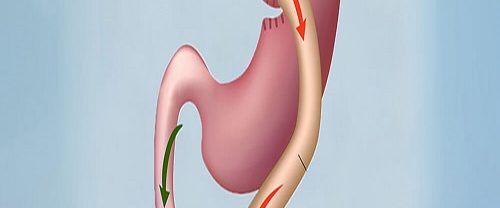

Tüp Mide Ameliyatı Nedir? Tüp mide ameliyatı, obezite problemi yaşayan bireylerde kilo kaybını desteklemek için uygulanan cerrahi bir prosedürdür. Bu operasyon, mideyi küçülterek ve sindirim sistemini değiştirerek kişinin daha az yemek yemesini ve dolayısıyla kilo vermesini sağlar. Bu ameliyat, genellikle kilo verme çabalarıyla sonuç alınamayan veya obeziteye bağlı sağlık sorunları yaşayan kişiler için bir seçenek…

Obezite Cerrahisi Nedir? Obezite cerrahisi, aşırı kilolu veya obez bireylerde kilo kaybını desteklemek için cerrahi prosedürlerin uygulandığı bir tıbbi alanı kapsar. Bu cerrahi işlemler, kilo kaybını teşvik ederek obezitenin sağlık üzerindeki olumsuz etkilerini azaltmayı amaçlar. Aday Seçimi ve Değerlendirme: Obezite cerrahisi adaylarının belirlenmesi için çeşitli kriterler vardır. Genellikle vücut kitle indeksi (VKİ) üzerinden değerlendirme yapılır…

Gastrik Bypass Ameliyatı Nedir? Gastrik Bypass Ameliyatı, aşırı obezite tedavisinde kullanılan bir cerrahi prosedürdür. Bu prosedürde, mide hacmi küçültülür ve sindirim sistemi yeniden düzenlenir. Temelde, iki farklı mekanizma ile kilo kaybını teşvik eder: Mide Hacminin Azaltılması: Gastrik Bypass sırasında, mide küçük bir torba haline getirilir. Bu torbanın hacmi genellikle 15 ila 30 mililitre arasındadır. Küçük…